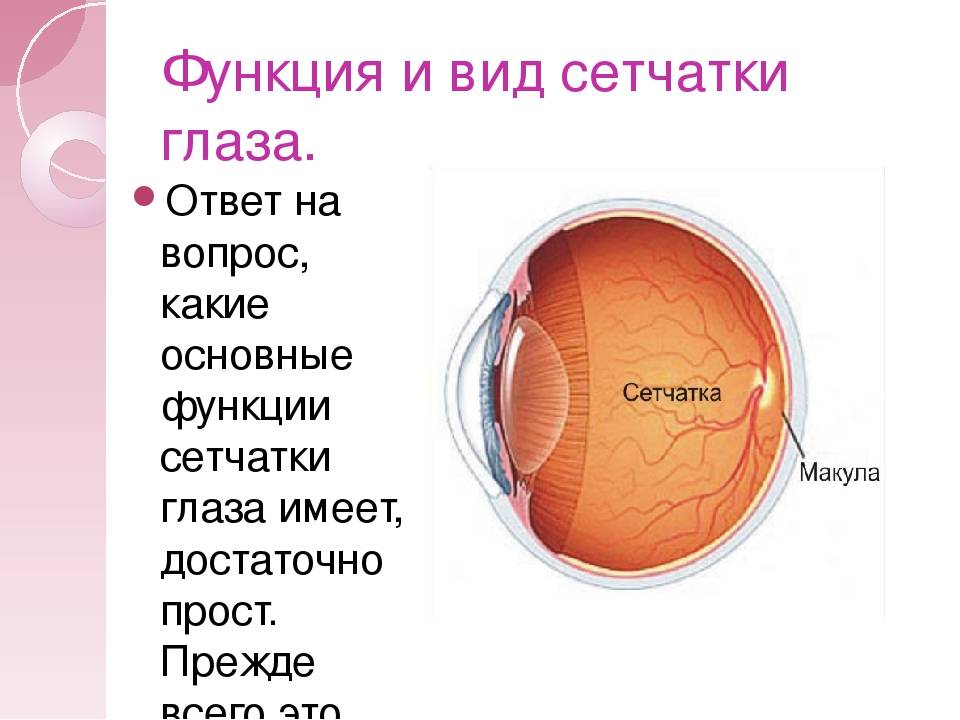

Изображения и анатомия сетчатки глаза

Раздел: Визуальный дайджест